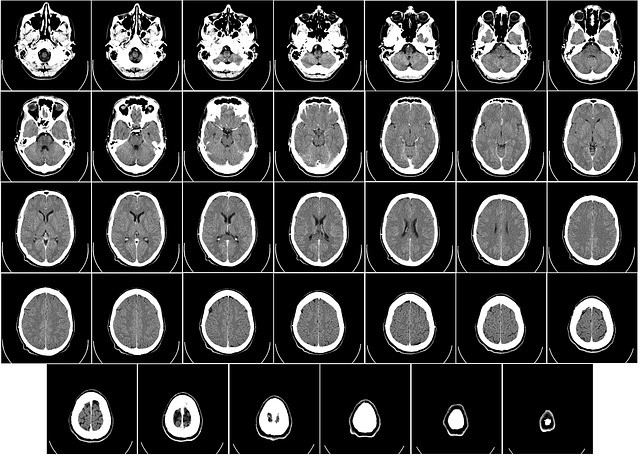

MRI (הדמיית תהודה מגנטית) ו-CT (טומוגרפיה ממוחשבת) הם שני סוגים שונים של טכניקות הדמיה רפואיות המשמשות ליצירת תמונות מפורטות של פנים הגוף. מה זה MRI? MRI משתמש בשדה מגנטי חזק, גלי רדיו ומחשב כדי ליצור תמונות מפורטות של פנים הגוף. הוא אינו משתמש בקרינה מייננת, שהיא סוג של קרינה שעלולה להזיק לגוף. MRI טוב מאוד … להמשך קריאה